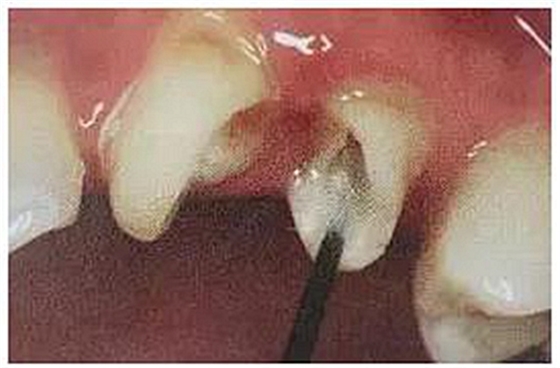

絢彩AT無飾瓷全形態(tài)氧化鋯產品體驗+全冠和嵌體微創(chuàng)修復后牙絢彩AT無飾瓷全形態(tài)氧化鋯產品體驗+全冠和嵌體微創(chuàng)修復后牙舌側牙體破壞至齦下,髓腔變色明顯。26經過與患者溝通降低咬合并做了根管治療。

絢彩AT無飾瓷全形態(tài)氧化鋯產品體驗+全冠和嵌體微創(chuàng)修復后牙從側面照可以看到26牙體變黑,頰側壁不足2mm,牙質脆弱。

第二步,拆除26舊修復體,因為密合度高,拆冠費了不少時間。

絢彩AT無飾瓷全形態(tài)氧化鋯產品體驗+全冠和嵌體微創(chuàng)修復后牙

拆冠對26的頰舌側肩臺有所破壞,牙齦少許損傷。暫時臨時牙修復保護基牙。